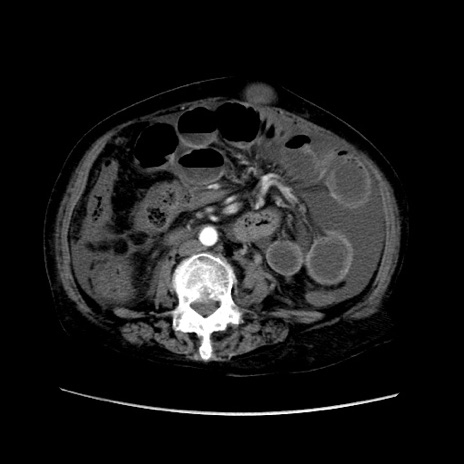

矢状断像

【症例】80歳代 女性

【主訴】腹部膨満感

【現病歴】他院にて肝硬変にてフォロー中。1週間前から便秘、腹部膨満感、臍部腫瘤あり受診となる。

【既往歴】肝硬変

【身体所見】腹部膨隆あり、皮膚変化なし、疼痛なし。

【データ】WBC 4600、CRP 0.25